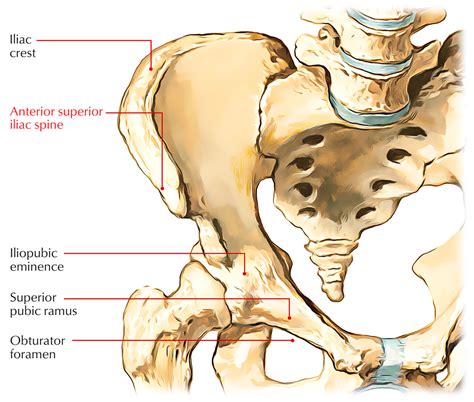

The ilium is the largest and uppermost section of the hip bone. When we look at the rim of the ilium—known as the iliac crest—there are two distinct bony projections at the front. The uppermost projection is known as the Anterior Superior Iliac Spine (ASIS), while the one situated slightly lower is the Anterior Inferior Iliac Spine (AIIS). Together, these two landmarks represent the Anterior Iliac Spine complex.

The ASIS serves as a primary attachment point for several muscles, including the sartorius muscle and the tensor fasciae latae (TFL), as well as the inguinal ligament. Meanwhile, the AIIS acts as the origin for the rectus femoris muscle, one of the four quadriceps muscles. Because these bony protrusions are essentially “anchor points” for major muscle groups, they are subject to significant mechanical stress during physical activity.